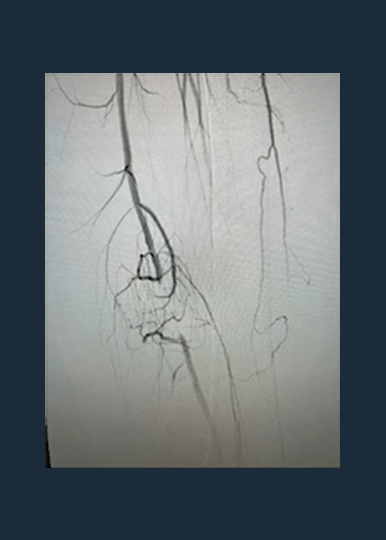

Shockwave M5+ is a versatile catheter, effective for above-the-knee (ATK) endovascular treatments.

The largest prospective real-world evidence for the treatment of complex, heavily calcified PAD